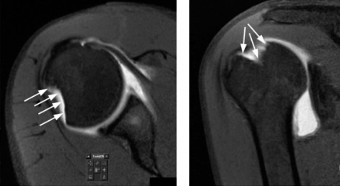

The correct answer is (B). An MRI showing a rotator cuff tear is considered diagnostic of a rotator cuff tear because of its high sensitivity, specificity, and accuracy. It has superb soft tissue imaging abilities (see Fig. 2–5). However, it should be noted that while MRI usually can differentiate between partial- and full-thickness rotator cuff tears, this varies with the power and accuracy of the MRI facility. This is also true with the ability of MRI to differentiate between partial-thickness rotator cuff tears and subacromial bursitis. An arthroscopy is needed for definitive differentiation of these pathologies.

Figure 2–5_Coronal oblique view MRI slice of a left shoulder. (Reproduced with permission from Smithius R and van de Woude HJ. Shoulder MR Anatomy: Normal Anatomy, Variants, and Checklist. _Radiology Assistant. April 2, 2012.)

Figure 2–8_Reproduced with permission from Stadnick ME. _Partial Rotator Cuff Tears. MRI Web Clinic. 2007 (Apr).

The correct answer is (A). These are best diagnosed on an MRI as seen in the imaging provided; addition of intra-articular contrast can further improve this study. Answer B, full-thickness rotator cuff tear, is incorrect as the bursal side of the tendon can be seen to be in continuity. Answer C, a SLAP lesion, will be visualized as a labral tear on a coronal MRI and will be found at the biceps root. Answer D, an ALPSA lesion, will be most clearly seen on an axial MRI. It is a variant of a Bankart lesion where the labrum is displaced medially and inferiorly rolling down the glenoid neck underneath the periosteum.

MRI remains the most popular imaging modality for diagnosing rotator cuff tears. Normal rotator cuff tendon appears dark on both T1 and T2 sequences. Tears may be noted as being full-thickness, articular-sided, bursal-sided, or intrasubstance. They are visualized as a disruption in the regular contour of the tendon and increased signal intensity on T2 sequences. Occasionally, an MR arthrogram may provide additional information regarding a cuff tear, although this is not routinely ordered.

What MRI sequence and plane is best for viewing supraspinatus rotator cuff tears?

The correct answer is (D). T2 sequence causes most soft tissues, including muscle and tendon, to appear dark and inflammation, such as at the site of a tear, to appear bright. This means that if there is a rotator cuff tear, there will be a bright spot along the course of the dark rotator cuff tendon. This is easiest to pick out in the coronal plane because the tendon runs in this plane, allowing one to view the entire supraspinatus tendon and tear in one cut.

Figure 2–9_From Shi LL, Mullen MG, Freehill MT, et al. Accuracy of Long Head of the Biceps Subluxation as a Predictor for Subscapularis Tears. _Arthroscopy 2015;32(4):615–619.

The correct answer is (A). Medial subluxation of the biceps tendon as seen in this MRI is commonly associated with a tear of the subscapularis tendon which attaches to the lesser tuberosity. This patient’s pain may in part be attributable to the subscapular tear and this should be evaluated for during physical examination. Supraspinatus tears (Answer B) cannot be easily visualized on axial views and are not associated with medial biceps subluxations. A labral tear and ALPSA lesion (Answers C and D) are not seen on the images provided. The question stem and MRI are not suggestive of shoulder instability (Answer E). Objectives: Did you learn...? Diagnose and treat acute rotator cuff tears?